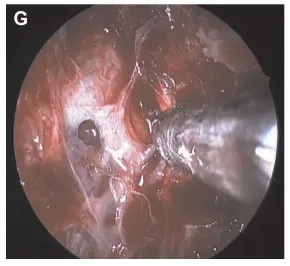

▼肿瘤逐渐被切除。在将脊索瘤与硬脑膜分离时,术中发生脑脊液漏(图G)。